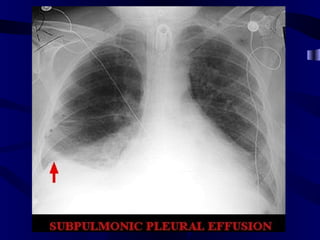

Small Pleural Effusion Normal: Sharp Angles Blunted posterior costophrenic sulcus